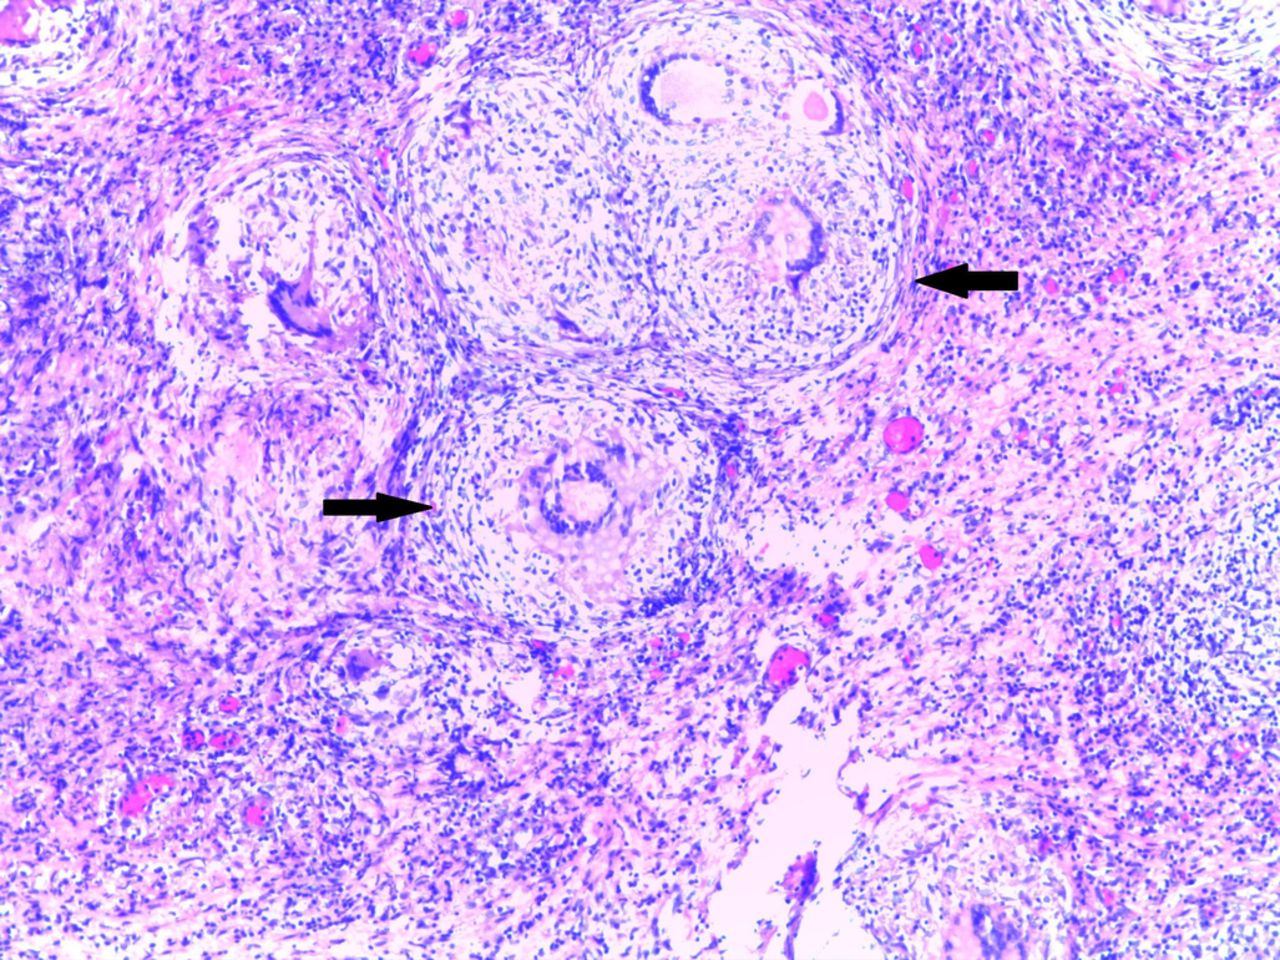

Hasil evaluasi kasus yaitu PTB pada seorang wanita berusia 20 tahun dengan riwayat rawat inap berulang kali di rumah sakit dengan kecurigaan tingkat Ca125 tinggi kista ovarium ganas. USG menunjukkan massa di rongga panggul. Laparotomi eksplorasi harus dilakukan dan biopsi mendukung diagnosis PTB yang dikonfirmasi dengan basil tahan asam dan hasil patologi.

Berbagai pemeriksaan penunjang diperlukan untuk menegakkan diagnosis yang tepat dan menyingkirkan diagnosis banding. USG dapat digunakan untuk mendeteksi asites rendah, kumpulan cairan, dan penebalan omentum dan peritoneum. CT-scan lebih disukai untuk mengevaluasi peritoneum dan jeroan intraabdomen. Kasus ini menggambarkan tantangan dalam menegakkan diagnosis PTB dengan gejala klinis yang tidak khas sehingga harus dilakukan pemeriksaan secara menyeluruh. Penegakan diagnosis yang tepat sangat penting dalam pemberian terapi.